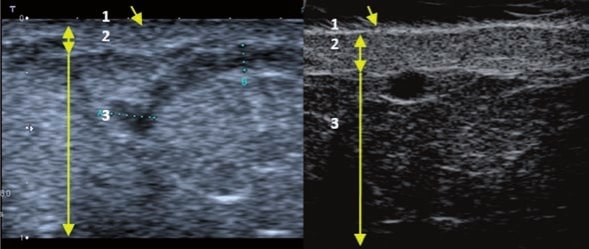

La ecografía Doppler permite obtener imágenes de grandes vasos y perforantes que suelen estar situados en las capas más profundas del tejido subcutáneo (fig. 1). Desgraciadamente, la ecografía convencional no es capaz de obtener imágenes de vasos más pequeños. Para visualizar los vasos más pequeños situados cerca de la superficie de la epidermis y en la capa superior del tejido subcutáneo, se utiliza el HFU (fig. 1). Gracias al uso de transductores con frecuencias superiores a 20 MHz, se obtiene una imagen ecográfica de alta resolución en la que podemos diferenciar estructuras menores de 0,1 mm. Sin embargo, cuanto mayor es la resolución, menor es la penetración del haz de ultrasonidos en las capas de la piel. Por lo tanto, dependiendo del transductor y del aparato, es posible penetrar en la piel hasta una profundidad de 20-30 mm como máximo. Tal penetración, junto con la alta resolución de la imagen, permite la evaluación incluso de vasos sanguíneos muy pequeños (fig. 2). Durante el examen con el uso de transductores de alta frecuencia, se puede evaluar con precisión el curso y la ubicación de los pequeños vasos en la piel. Esto es particularmente relevante para la selección del método de cierre del vaso y la planificación del procedimiento ya que, en la práctica, la superficie de la piel muestra muy a menudo únicamente un pequeño número de vasos o un ligero fragmento de un vaso; solo tras el examen por ecografía podemos determinar su número y curso reales. Para un cierre eficaz del vaso, es necesario hacerlo en toda su longitud. No debe limitarse al fragmento visto «a simple vista» en la superficie de la piel, ya que el cierre del fragmento causará su rápida recanalización(7). Con frecuencia, el vaso visible en la superficie de la piel cambia su curso, se vuelve más tortuoso y se desplaza a las capas más profundas de la piel(8). Por lo tanto, el curso de la vena y las perforantes deben conocerse y determinarse bien antes del procedimiento. El HFU también permite obtener imágenes de las perforantes entre pequeños vasos. Además, aparte de la evaluación del curso y la anatomía, la imagen ecográfica, gracias al software de ultrasonidos, también permite determinar los parámetros básicos como el diámetro del vaso, el grosor de su pared, la profundidad en la piel así como la presencia o ausencia de perfusión en el interior del vaso(6) (fig. 3). Gracias al transductor electrónico multielemento con la frecuencia de 40 MHz introducido en el mercado por Ultrasonix, también es posible visualizar la perfusión en los vasos en el modo Doppler color (fig. 4).